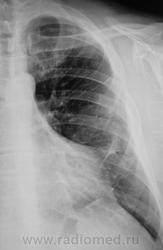

Понял, а не допускаете мысли, что могла быть операция на лёгком с резекцией ребра ( хорошо виден фрагмент заднего отрезка V ребра слева, с абсолютно нормальной костной структурой, что нехарактерно для метастатического поражения ребра ).

Коллеги, не вижу V ребра слева ( это мне подсказал, коллега который просматривает сайт). Как это расценивать?

Ребра не видно. Передайте коллеге, что он прав.